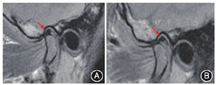

由于关节盘为软骨,含水量(即质子含量)较少,因此在所有序列上均为低信号,以质子密度加权成像(proton density weighted imaging,PDWI)最为显著。PDWI图像上关节盘高信号提示退变可能,其中后带表现最为显著(图3)。